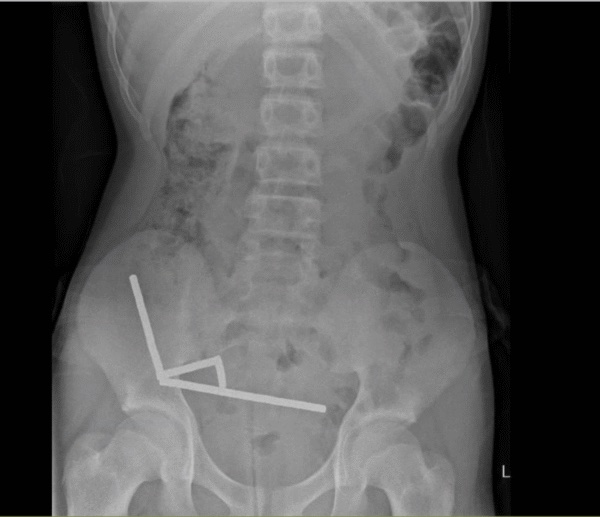

Életmentő műtéten esett át egy új-zélandi tinédzser, aki veszélyes online kihívást teljesített. A tizenéves közel 200 mágnest nyelt le, azok azonban összekapcsolódtak a beleiben, és szövetelhalást okoztak.

Életveszélybe került egy 13 éves új-zélandi fiú, miután közel 200 mágnest lenyelt, ezzel súlyos sérülést okozva a bélrendszerében – írja a Science Alert.

A tinédzser hasi panaszokkal ment a Tauranga Kórházba, ahol az orvosoknak elmondta, hogy egy héttel korábban körülbelül 100 darab mágnest nyelt le. Az orvosok az azonnali műtét mellett döntöttek, a feltárás során azonban kiderült, hogy a tizenéves közel 200 mágnest nyelt le.

A mágnesek egymáshoz tapadva összesen 4 láncot alkottak, amiket az orvosok a fiú bélrendszerének különböző szakaszaiból emeltek ki. A mágnesek több szövetben is nekrózist okoztak, a szövetelhalás miatt az orvosok a bélrendszer egy részét eltávolították.